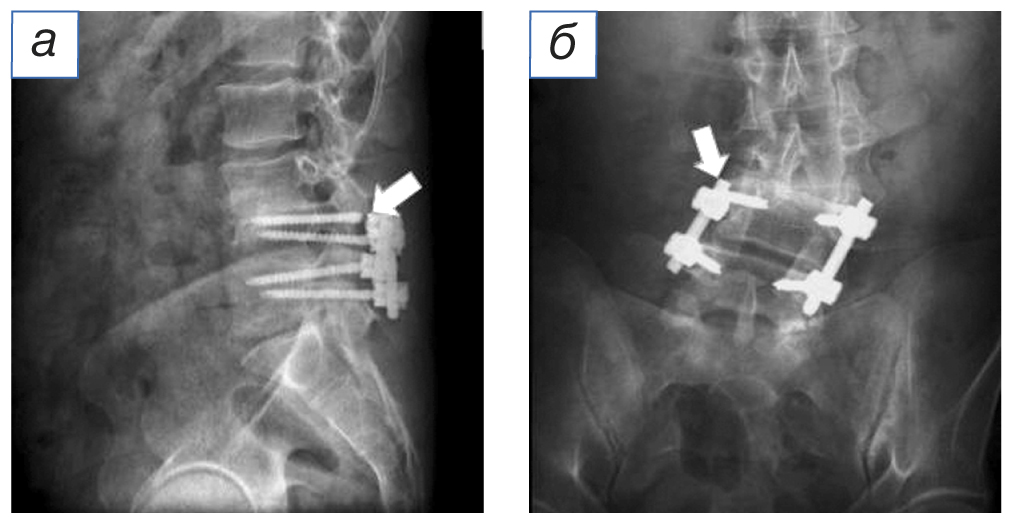

Через 5 лет после операции возобновились боли в области поясницы, правой и левой нижних конечностях, возникла слабость в левой стопе. При контрольном обследовании (рентгенография, мультиспиральная компьютерная томография и магнитно-резонансная томография) поясничного отдела позвоночника выявлены перелом правого верхнего винта системы транспедикулярной фиксации, стенозирование позвоночного канала на уровне LIII–LIV (рис. 1–3).

Рис. 1. Магнитно-резонансная томография в T2-режиме: а (сагиттальный срез) — область дегенеративно-дистрофических изменений позвоночно-двигательного сегмента над стабилизированным сегментом (стрелка); б (аксиальный срез) — параартикулярная киста, вызывающая фораминальный стеноз на уровне LIII–LIV справа (стрелка).

Fig. 1. Magnetic resonance imaging in T2-mode: а (sagittal section) — the area of degenerative-dystrophic changes in the spinal motion segment above the stabilized segment (arrow); б (axial section) — paraarticular cyst causing foraminal stenosis at the LIII–LIV level on the right (arrow).

По результатам магнитно-резонансной томографии выявлены признаки дегенеративно-дистрофических изменений поясничного отдела позвоночника, левосторонний поясничный сколиоз, параартикулярная киста со стенозированием межпозвонкового отверстия на уровне LIII–LIV справа.